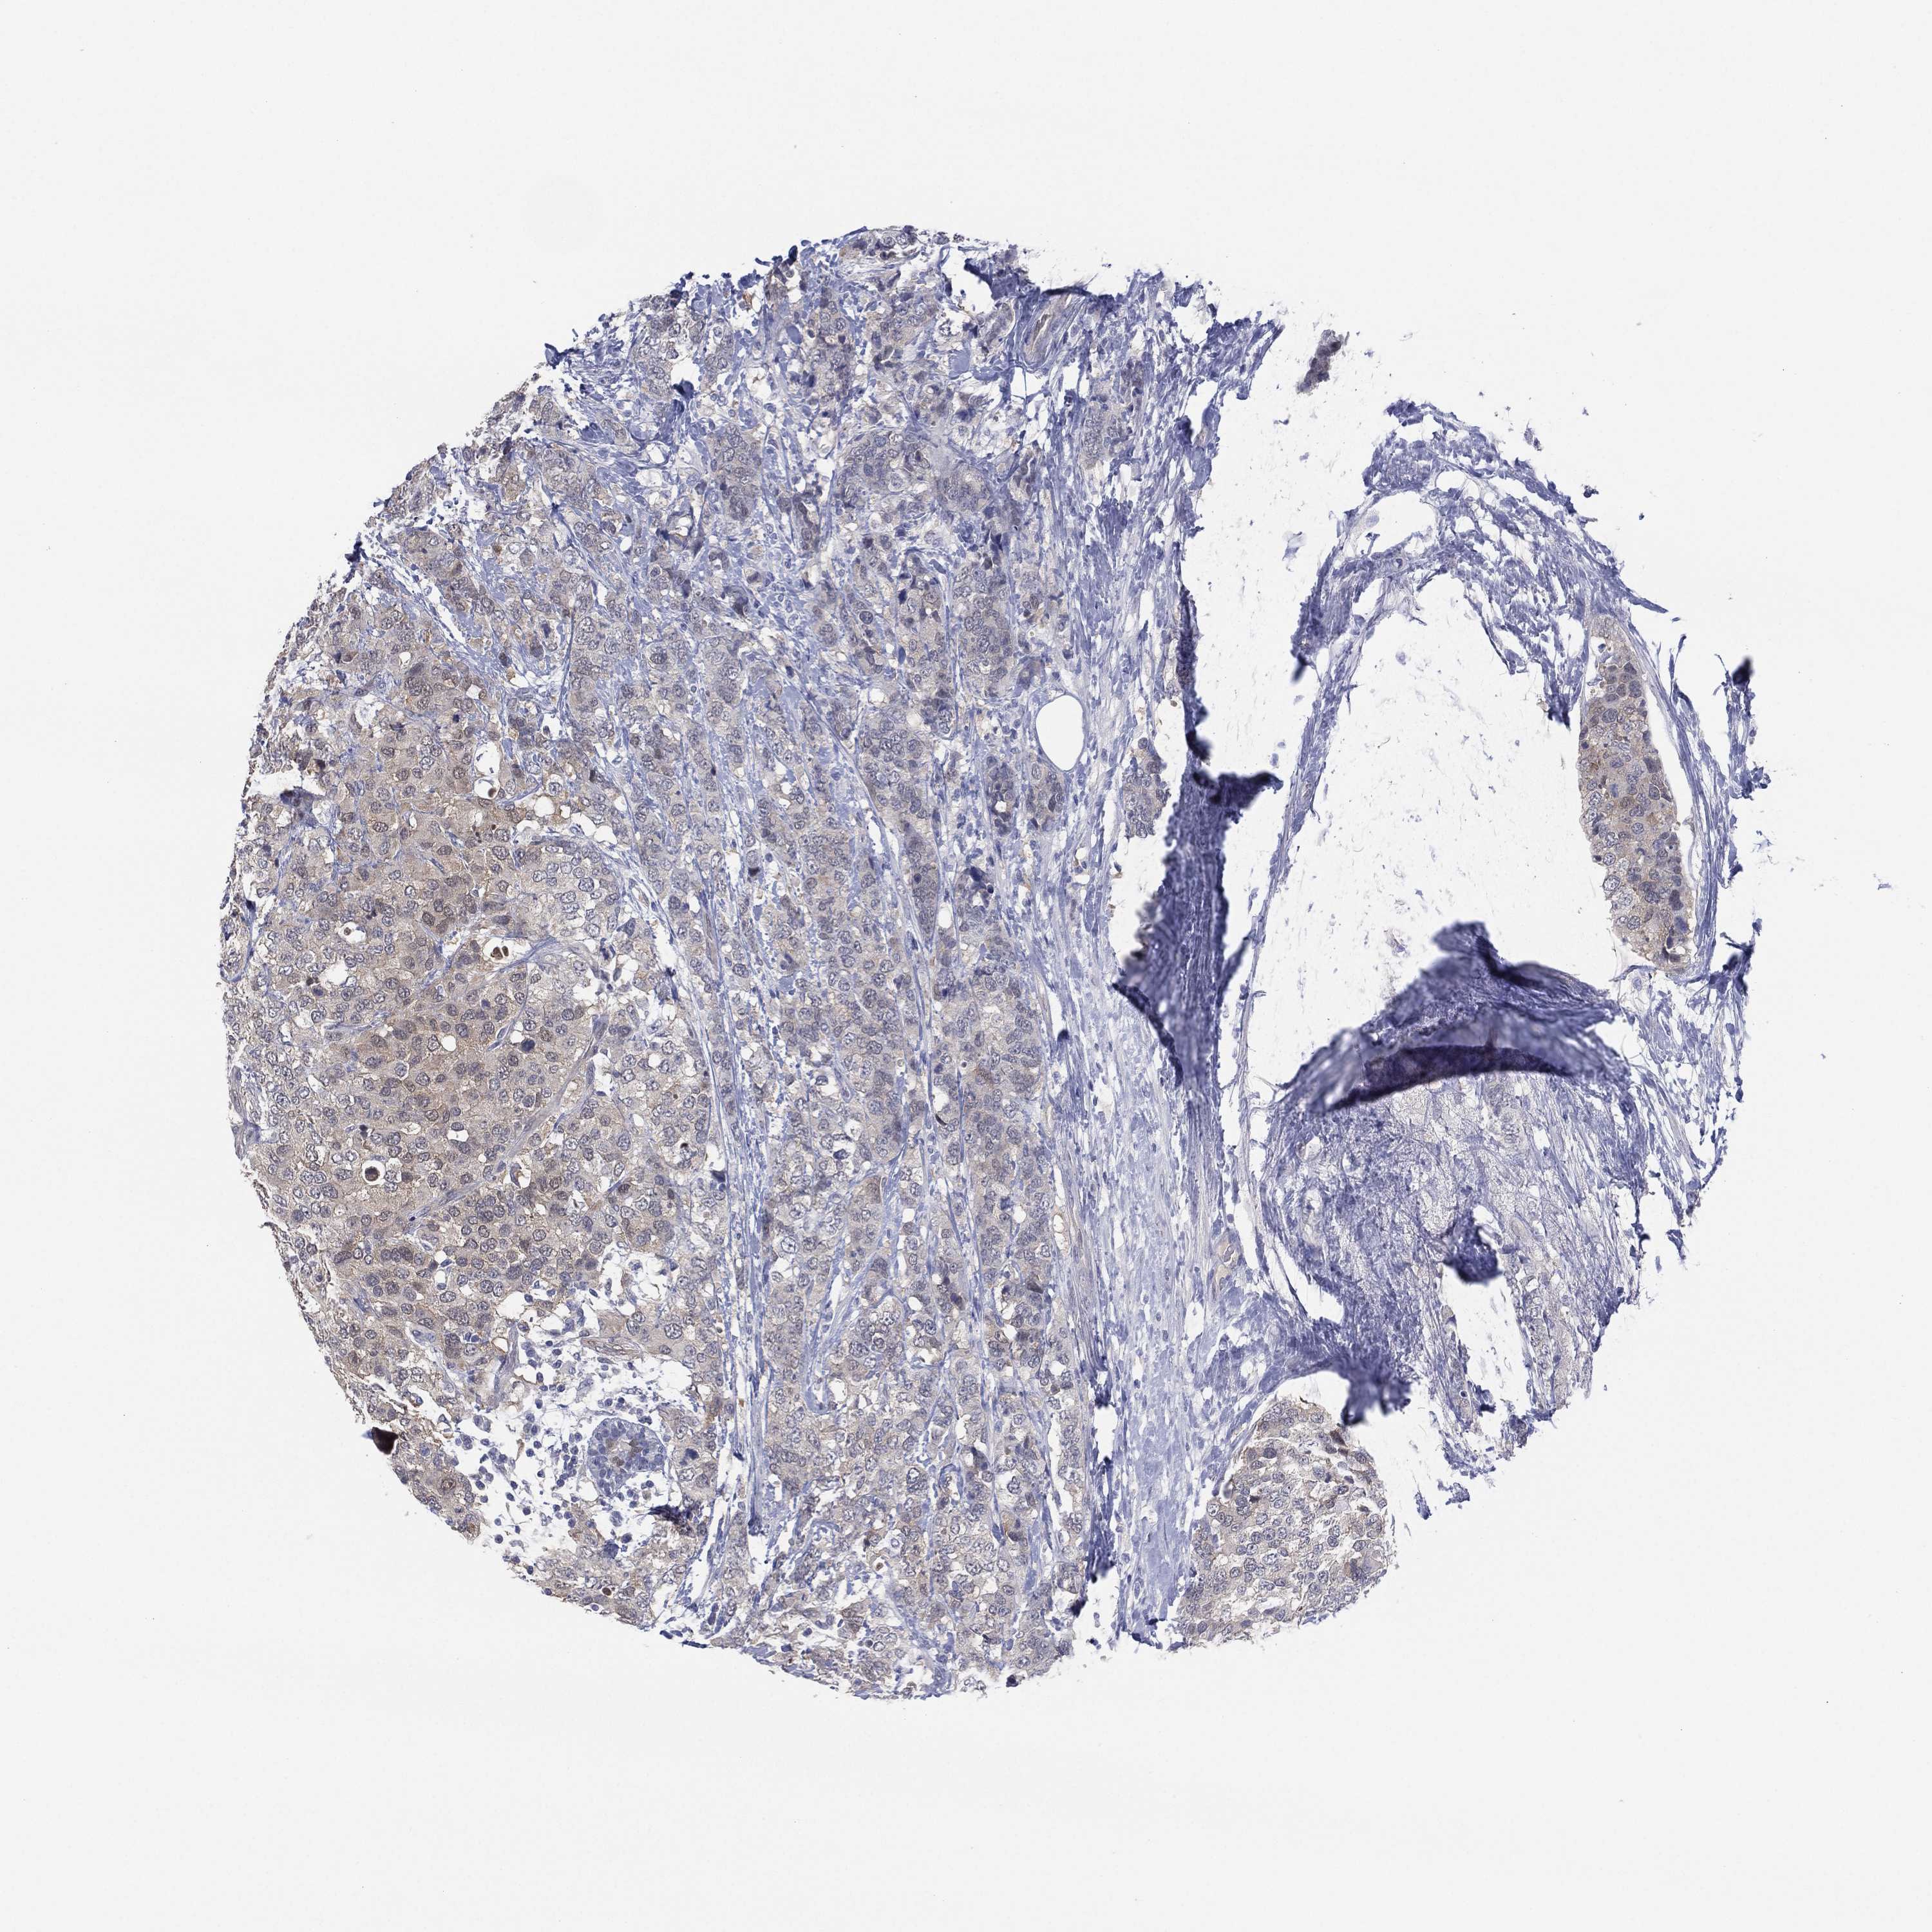

CANCER BREAST CANCER Show tissue menu

BRCA TCGA BRCA VALIDATION PROTEIN EXPRESSION

ANTIBODIES

AND

VALIDATION